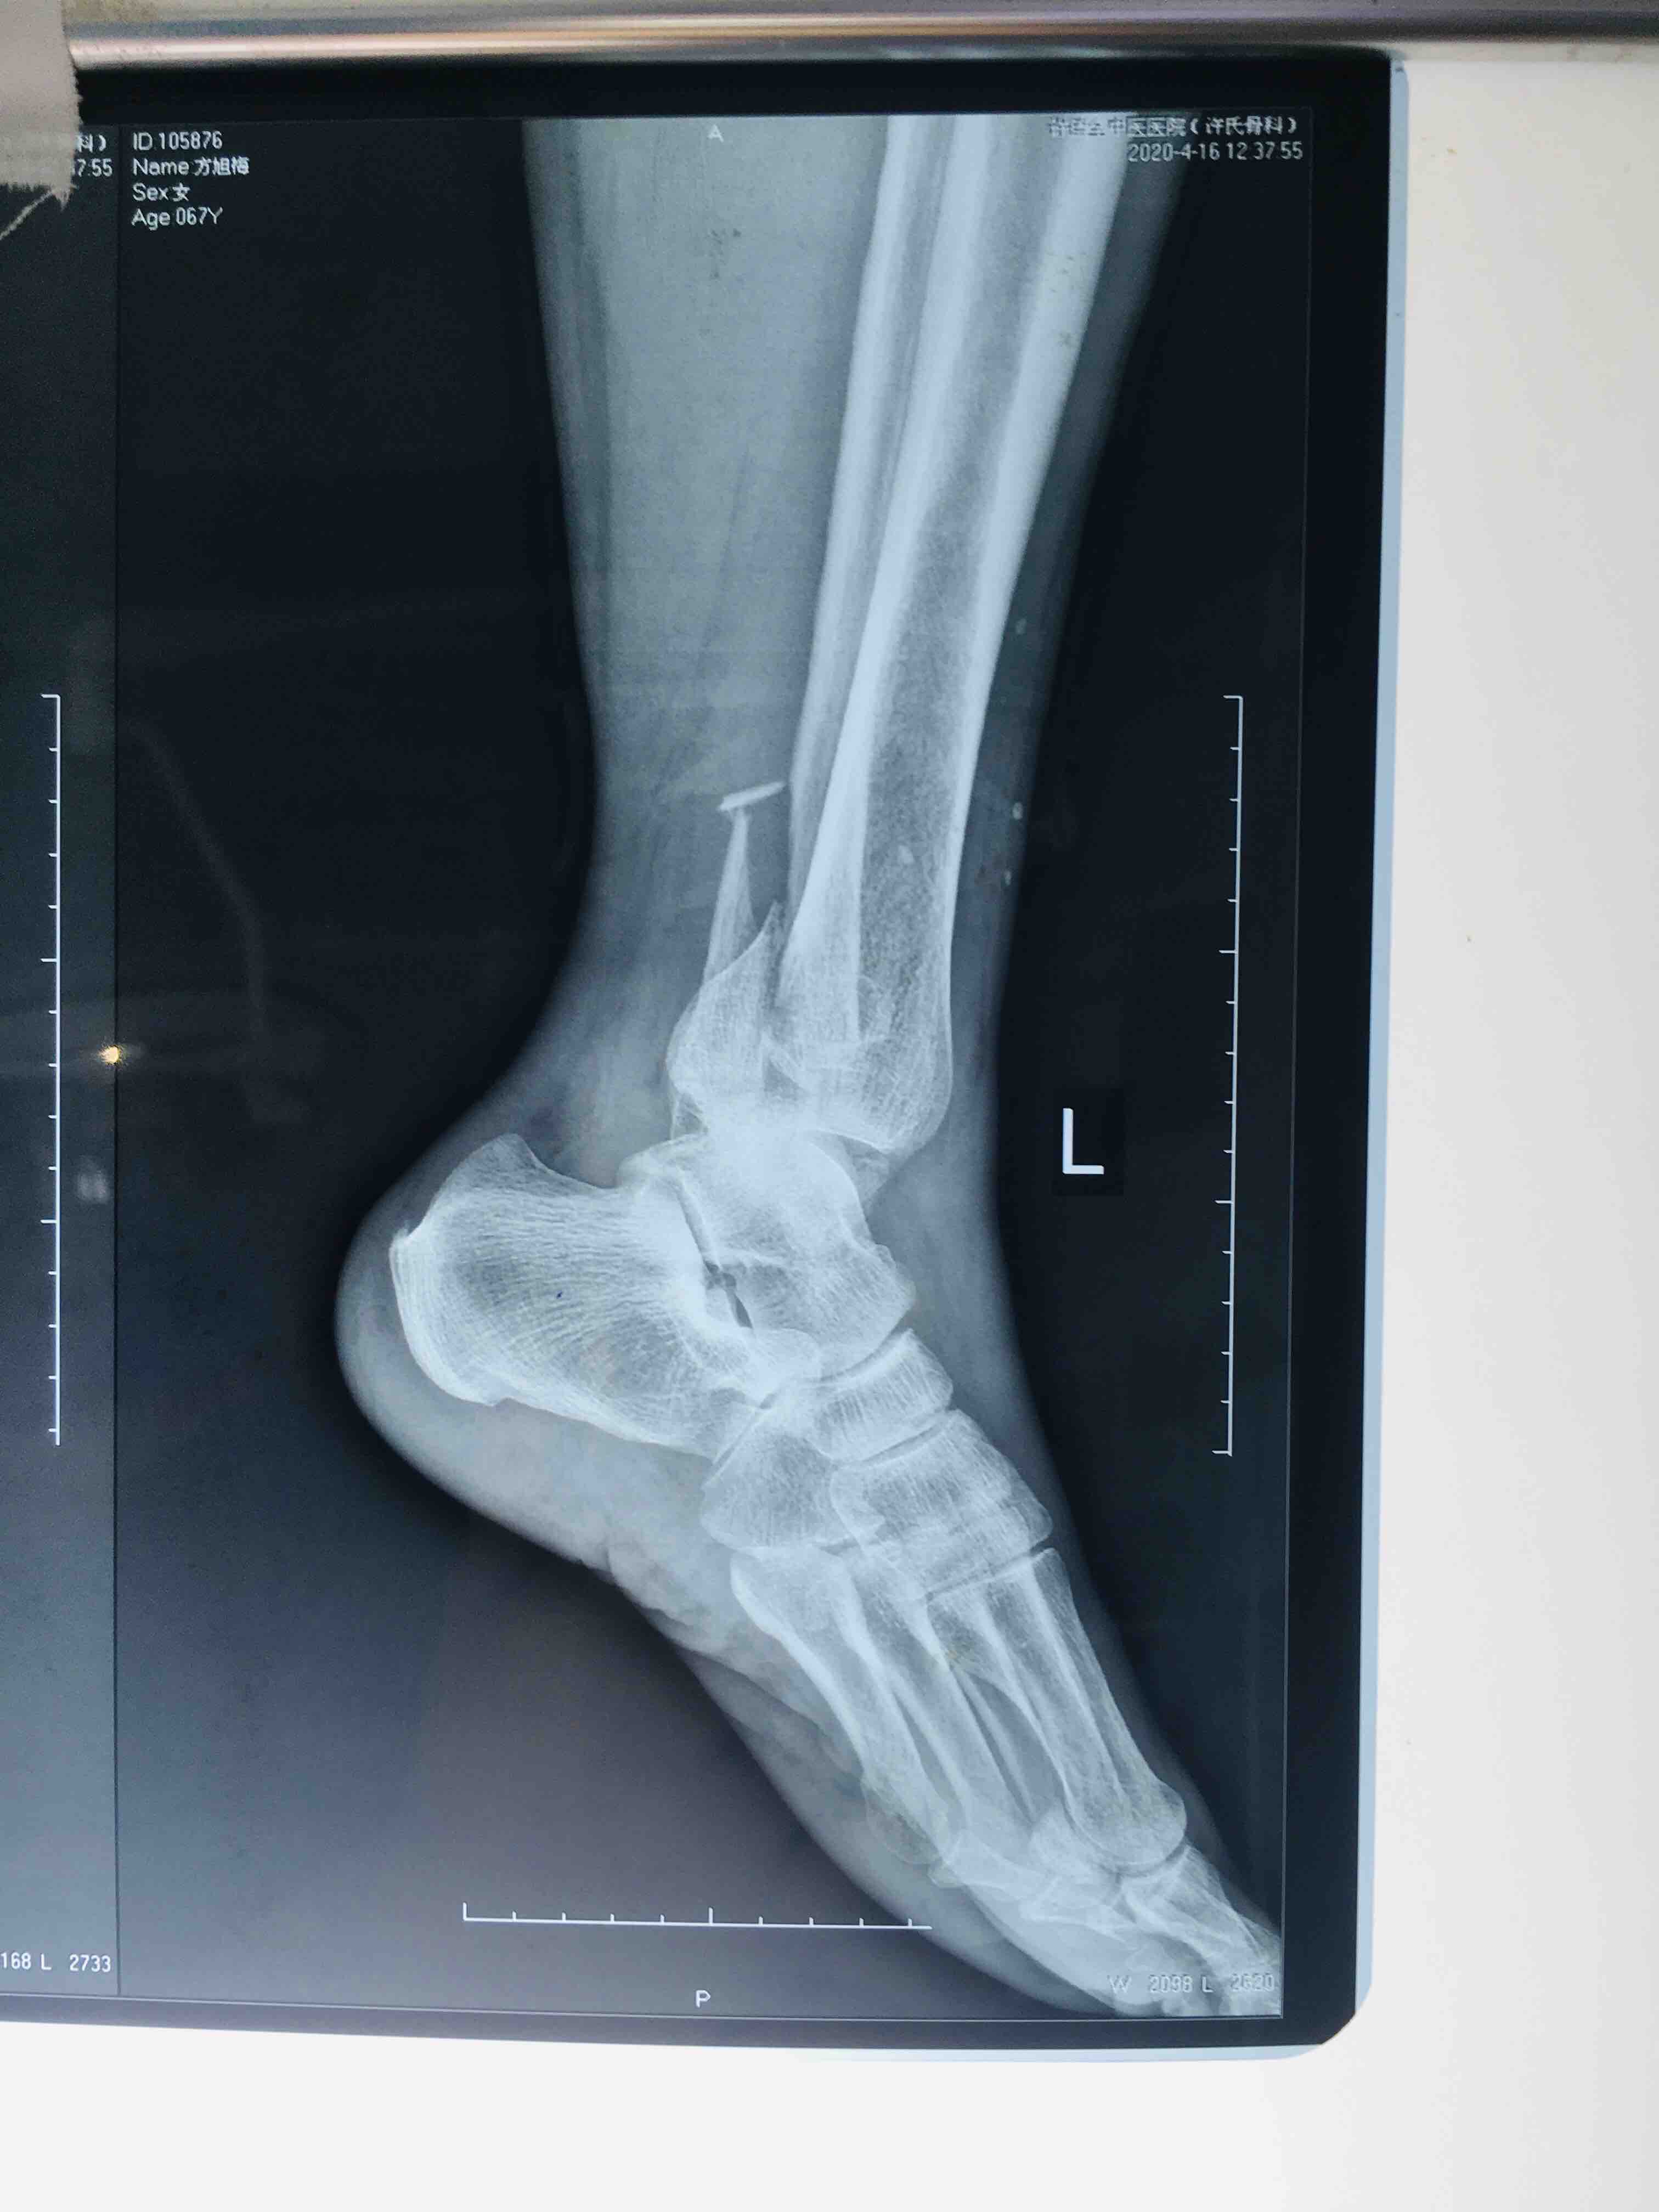

三踝粉碎性骨折(切复内固定术)

摔伤后左踝肿胀,疼痛,活动受限1小时入院。既往身体状况一般。无特殊不良癖好。

生命体征平稳,心肺复未见异常。左踝肿胀明显,畸形,局部皮色发红,皮温高,压痛及纵向叩击痛阳性,末梢血运感觉正常。

急诊行骨牵引,消肿等处理,在腰麻下行切复内固定术,术后抗炎,消肿。